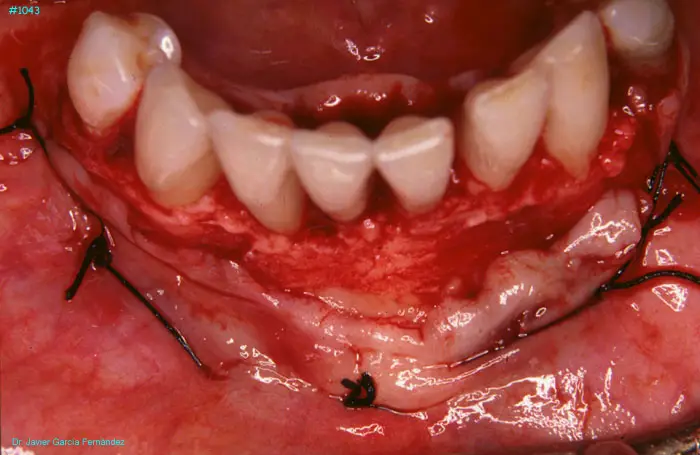

Atlas of Surgical Techniques in Periodontics. Chapter III. Atlas de Técnicas Quirúrgicas en Periodoncia